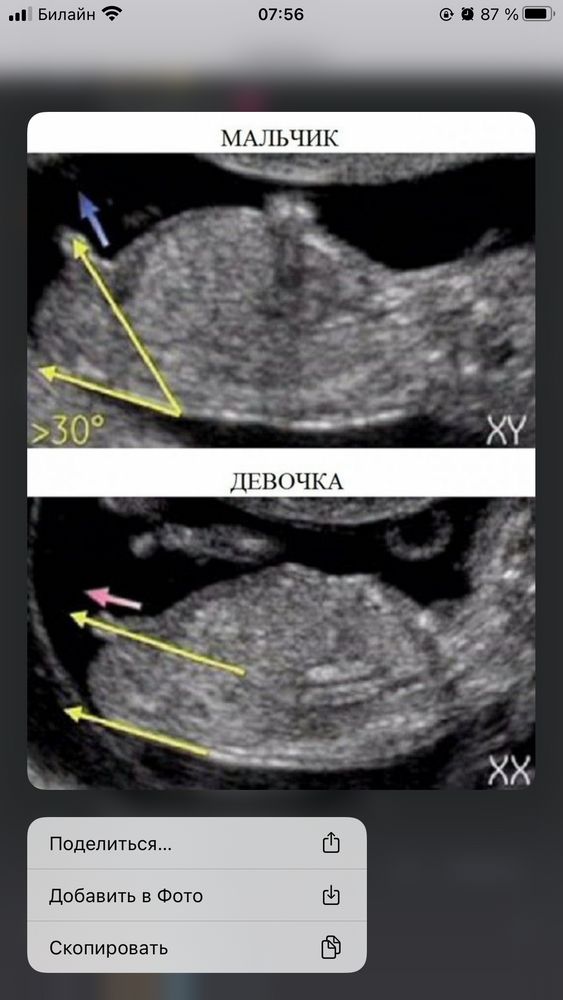

Я руководствовалась по вот этой фотографии, у меня совпало. Мне кажется перед нами принцесса 🫣